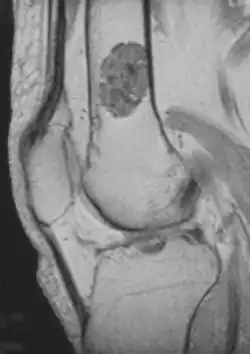

- magnetic resonance imaging (MRI)[7] – a diagnostic procedure that uses a combination of large magnets, radiofrequencies, and a computer to produce detailed images of organs and structures within the body. This test is done to rule out any associated abnormalities of the spinal cord and nerves.